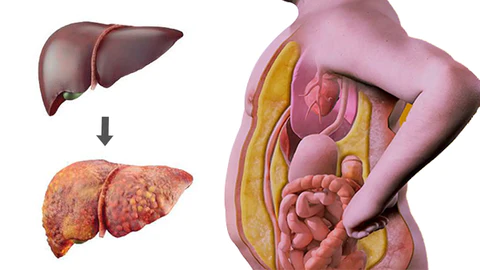

AAFQ™ Polygonum Multiflorum and Ginseng Extract Herbal Spray is specifically formulated to address conditions such as fatty liver, alcoholic hepatitis, liver fibrosis, obesity, insomnia, cirrhosis, hair loss, jaundice, gallbladder disease, and liver dysfunction. Our formula is designed to provide powerful liver support through sublingual absorption, activating liver cell regeneration, repairing the liver, enhancing detoxification capabilities, reducing inflammation, and decreasing visceral fat. By using our spray, you can expect increased energy and vitality within 8 weeks, helping you regain robust liver detoxification function.

AAFQ™ Polygonum Multiflorum and Ginseng Extract Herbal Spray is specifically formulated to address conditions such as fatty liver, alcoholic hepatitis, liver fibrosis, obesity, insomnia, cirrhosis, hair loss, jaundice, gallbladder disease, and liver dysfunction. Our formula is designed to provide powerful liver support through sublingual absorption, activating liver cell regeneration, repairing the liver, enhancing detoxification capabilities, reducing inflammation, and decreasing visceral fat. By using our spray, you can expect increased energy and vitality within 8 weeks, helping you regain robust liver detoxification function.